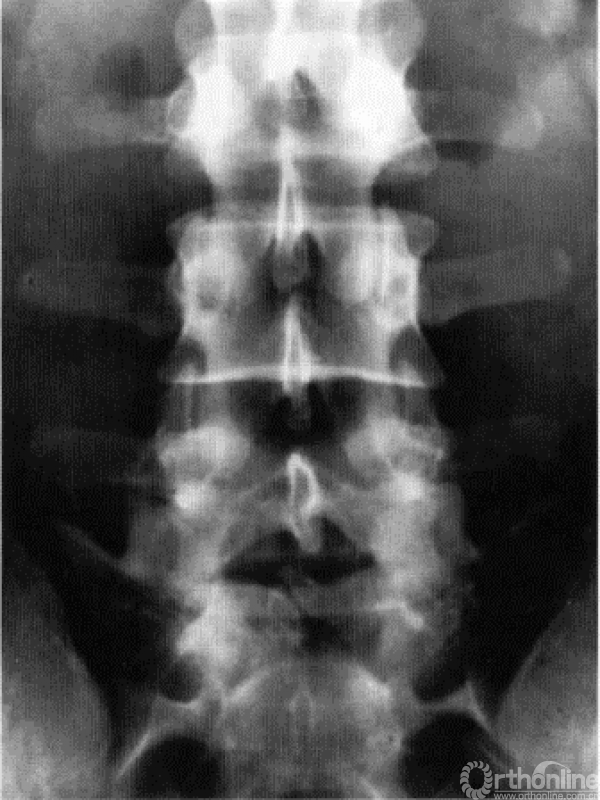

图18.12 正位X线片显示3层分区与后方解剖结构的重叠关系。注意L5椎板下缘(与椎间隙无重叠)与L3椎板下缘(其椎板的下缘重叠到L4的第3层)与前方3层分区重叠关系的变化